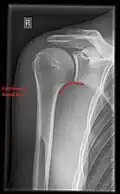

Fractures of shoulder bones can include clavicular fractures, scapular fractures, and fractures of the upper humerus.

X-ray

Projectional radiography views of the shoulder include:

- AP-projection 40° posterior oblique after Grashey

The body has to be rotated about 30 to 45 degrees towards the shoulder to be imaged, and the standing or sitting patient lets the arm hang. This method reveals the joint gap and the vertical alignment towards the socket.[26]

- Transaxillary projection

The arm should be abducted 80 to 100 degrees. This method reveals:[26]

- The horizontal alignment of the humerus head in respect to the socket and the lateral clavicle in respect to the acromion

- Lesions of the anterior and posterior socket border, or of the tuberculum minus

- The eventual non-closure of the acromial apophysis

- The coraco-humeral interval

- Y-projection

The lateral contour of the shoulder should be positioned in front of the film in a way that the longitudinal axis of the scapula continues parallel to the path of the rays. This method reveals:[26]

- The horizontal centralization of the humerus head and socket

- The osseous margins of the coraco-acromial arch and hence the supraspinatus outlet canal

- The shape of the acromion

This projection has a low tolerance for errors and, accordingly, needs proper execution.[26] The Y-projection can be traced back to Wijnblath’s 1933 published cavitas-en-face projection.[27]

-

CR. shoulay film. -

Transaxillary conventional radiography -

Y-projection conventional radiography